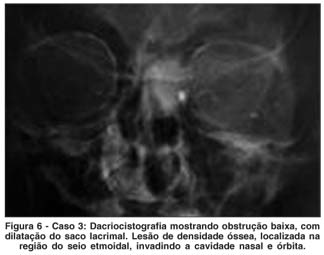

O exame ocular era normal. À ectoscopia havia nódulo móvel, indolor, consistência fibroelástica, no canto nasal do OE. Expressão sobre o saco lacrimal provocava a saída de secreção esbranquiçada. A dacriocistografia mostrou lesão no canto interno do OE, dilatação e obstrução baixa da via lacrimal (Figura 6). Portanto, havia uma dilatação do saco lacrimal, provavelmente secundária à lesão que foi evidenciada na tomografia, sendo também observada a lesão de densidade óssea, localizada no seio etmoidal e invadindo cavidade nasal, compatível com osteoma do etmóide (Figura 7A e B).